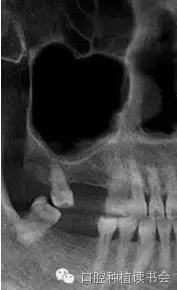

上頜竇氣化的現(xiàn)象主要來自先天因素和生理病理性因素,有的病人雖然年輕,但上頜竇腔較大,后牙牙根幾乎伸進上頜竇。隨著年齡增大、磨牙缺失,由于上頜竇處于負壓狀態(tài),尤其是缺牙后缺少來自牙槽脊的功能刺激,氣化現(xiàn)象會更嚴重,加之原有竇腔較大,就表現(xiàn)為巨大的上頜竇腔,甚至竇底與鼻底在同一水平(圖2)。有研究表明,上頜竇容積在青少年階段隨年齡而變化,中老年階段達到穩(wěn)定狀態(tài),氣化系數(shù)無增齡性改變。上頜竇竇腔平均最大容積為:38*33*38mm(Chih-Long,2014)。上頜竇容積和牙槽骨骨量呈負相關(guān),上頜牙全部脫落促進上頜竇變形,上頜竇容積有減小趨勢。上頜骨的老化特點是一個漸變的過程,步入中年期開始進行重塑,而老年期上頜骨形態(tài)變化較小。

▲(圖2)